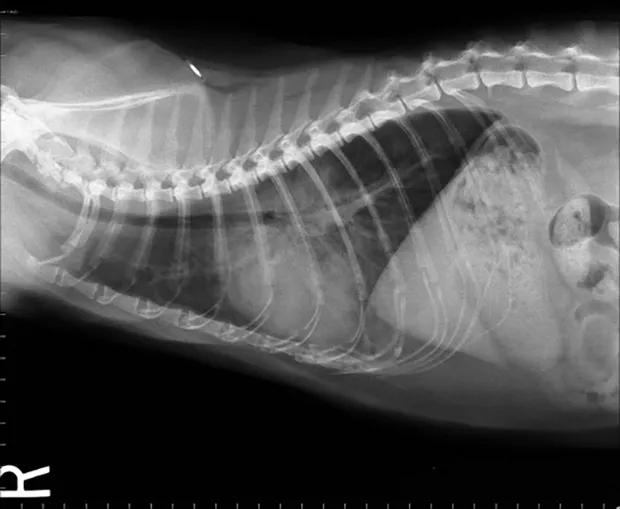

Feline lateral thoracic radiograph.

The following images exhibit commonly diagnosed emergency feline respiratory diseases. Match the image with the description of the disease process.